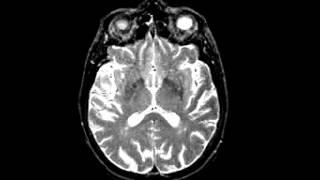

Cerebrovascular Disease Multiple embolic infarction, diffusion and FLAIR imaging

DR. DONG-KYUN KIM

Dr Dong Kyun Kim. Смотреть видео: Degenerative Disease Alzheimers Dementia, Metastatic Carcinoma Of The Colon Spatial, Cerebrovascular Disease Fatal Stroke, Neoplastic Disease Metastatic Adenocarcinoma.